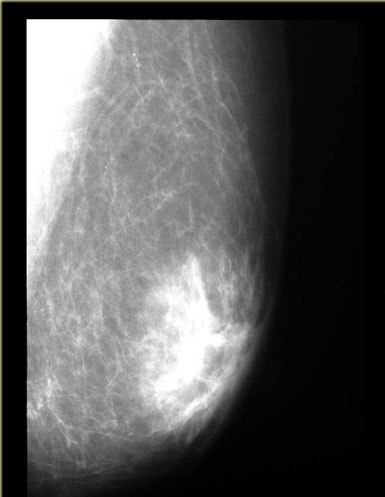

Киста молочной железы

Киста молочной железы встречается у 50% женщин репродуктивного возраста, у мужчин встречается достаточно редко. Размеры могут меняться в зависимости от фазы менструального цикла.

В молодом возрасте с целью инструментальной диагностики предпочтение отдается УЗИ молочных желез. У пациенток с иволютивными изменениями, возможно проведение маммографии.

Принято различать простые (гомогенные) и сложные (гетерогенные) кисты молочных желез. Простые кисты небольших размеров могут наблюдаться в динамике и не имеют злокачественного потенциала. Хирургическое лечение показано в случаях неэффективности консервативной терапии.

простая киста молочной железы.